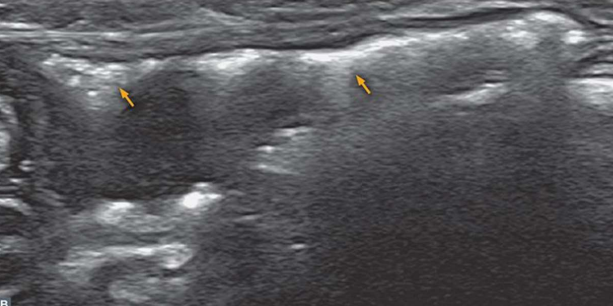

| Ultrasonography (Abd) | _Pyelonephritis |

|---|---|

| - 대표적으로 일시적인 콩팥 비대 (renal pelvic dilation) - Ureteral dilation (요관 확장) - Blunting of the renal papilla (콩팥유두의 둔화) - Echogenic debris (내부에 고에코성 잔해) * 신우신염인데 콩팥이 축소되어 있으면, CKD나 만성 신우신염을 의심해보자. + Bacterial culture : pyelocentesis(신우천자)는 실질을 건드릴 수 있으니, 방광 sampling부터 시도 |